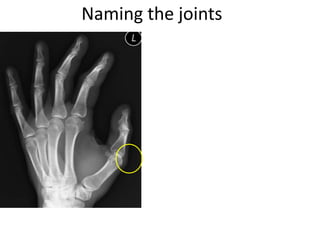

- Naming the bones, joints, tendons, nerves and skin landmarks of the hand and wrist.